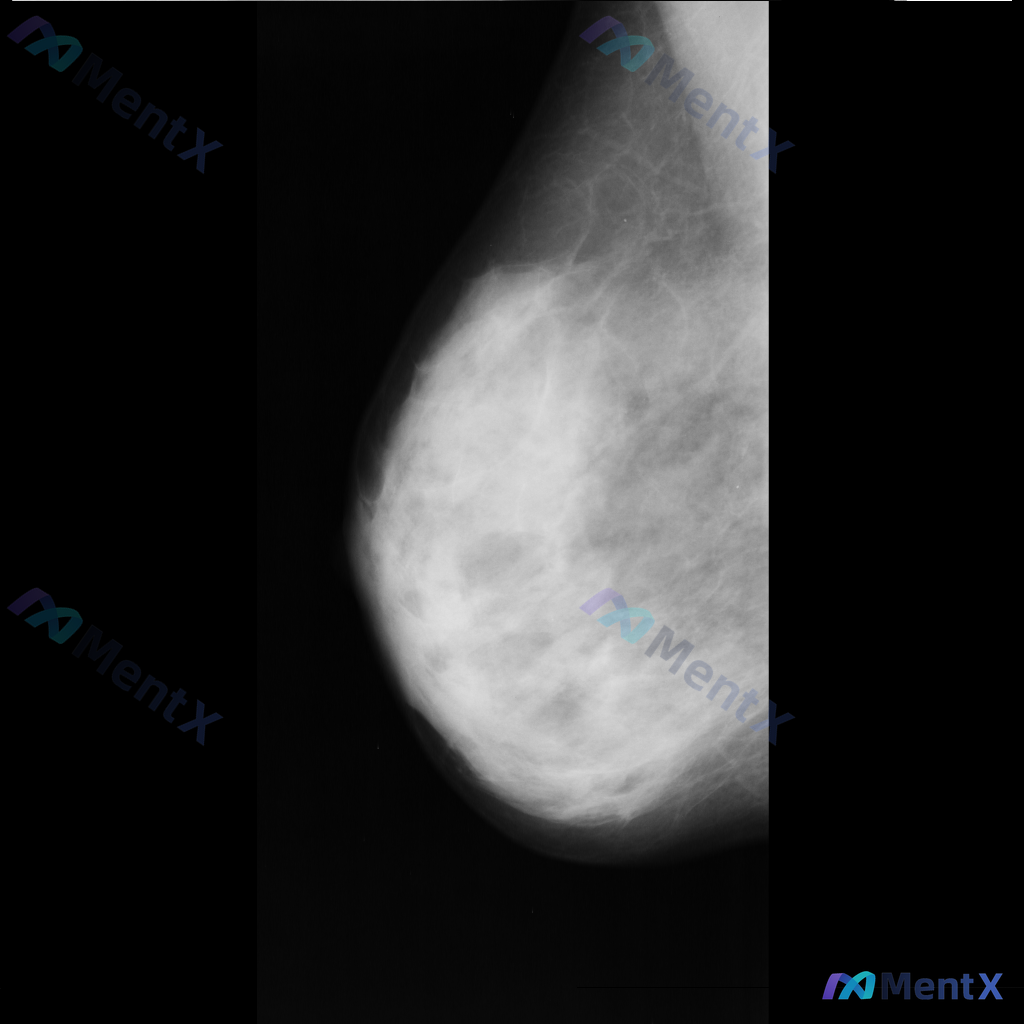

整理到一份右侧乳腺钼靶的影像资料,先和大家说一下表现: - 背景为不均匀致密型乳腺 - 右侧乳腺中部偏上区域可见局限性、成簇的细小多形性钙化 - 钙化区域周围可见局部密度略增高/结构异常的表现 目前还没有进一步的检查结果,单看这组影像表现,大家会优先往哪个方向考虑?后续评估思路是什么?